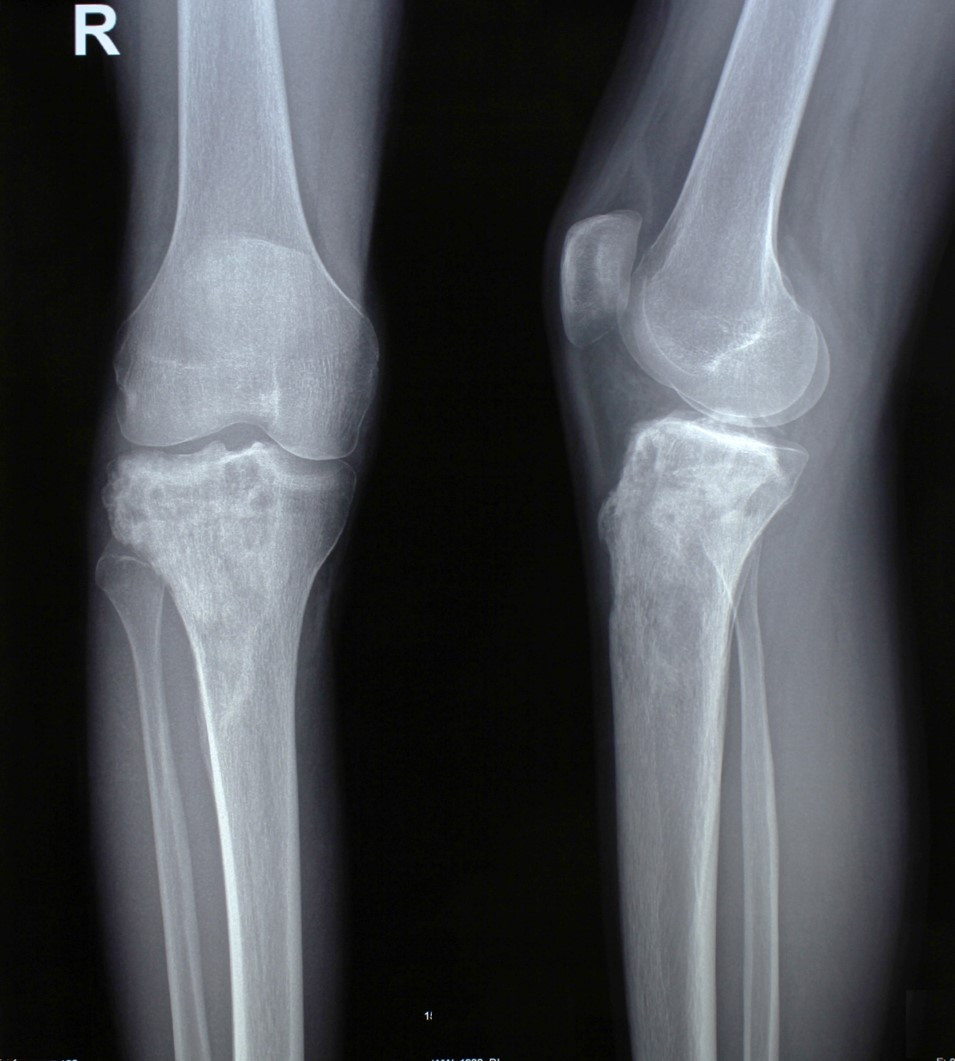

3. Метастаз в верхнюю часть бедренностой кости (первичная опухоль – рак легкого).

Пациентка 68 лет с ранее диагностированным раком легкого, получала химиотерапию, во время которого появились боли в тазобедренном суставе. В результате обследований был выявлен единичный метастаз в верхней трети бедренной кости с угрозой патологического перелома. Учитывая положительную реакцию организма на химиотерапию, чувствительность опухоли к лекарственным препаратам, была проведена радикальная операция. Во время операции была удалена верхняя треть бедренной кости, возникший дефект был восстановлен модульным биполярным эндопротезом, который позволяет сразу в зависимости от размера костного дефекта в ходе одной операции по принципу конструктора Lego восстановить дефект. Пациентка в дальнейшем получала послеоперационную химиотерапию, была предотвращена угроза патологического перелома, устранены боли, восстановлена функциональная пригодность оперированной конечности.

До операции

После операции